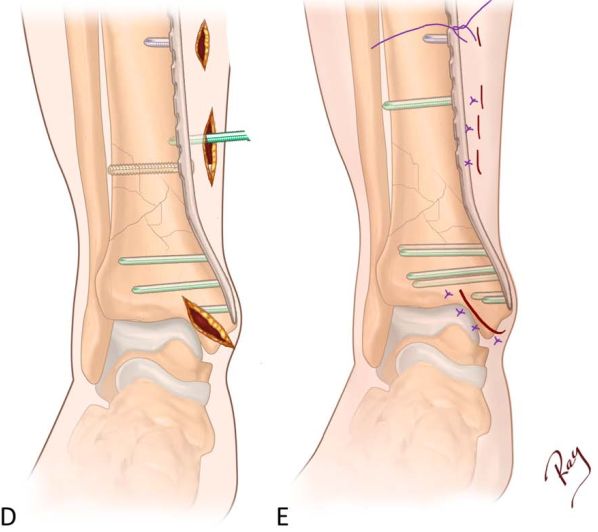

患者仰卧位,通常可通过手法牵引复位骨折,随后直接固定胫骨。若腓骨骨折粉碎程度较轻,可考虑先对腓骨进行切开复位内固定,以帮助胫骨复位并稳定,再行MIPO 术。腓骨固定时,在骨折部位做切口,采用1/3管状接骨板固定。胫骨固定时,在内踝尖端作一自前上方至后下方的30mm斜切口(图A):

该斜切口可向干骺端前方和关节面延长,以便直接复位该平面内的任何简单关节内劈裂骨折。随后可从内向外植入拉力螺钉,在接骨板沿胫骨向上滑动前实现关节面的加压。若劈裂骨折位于其他平面,可在骨折正上方另做一有限切口。仔细分离皮下组织后,可见一层薄的纤维组织,钢板应插入该层下方、骨膜上方,并向近端滑动。将钻头导向器连接至接骨板的最远端孔,作为接骨板插入的手柄。将接骨板置入剪刀分离出的间隙内,沿骨膜上方近端滑动(图B)。通过触诊确定接骨板沿胫骨皮下缘的位置,需避免接骨板向后滑动倾向。第一步需准确定位接骨板远端,其应延伸至内踝中点左右,但不宜达到内踝尖端。借助C臂机确认位置无误后,通过已安装的钻头导向器植入临时克氏针,将接骨板固定于远端干骺端。下一步评估接骨板近端的矢状位位置,可通过在接骨板近端易触及或C臂机可见的部位做一小切口轻松完成。此时需确认骨折已复位,尤其是长度和旋转对位良好,然后用另一枚临时克氏针固定接骨板近端。接骨板两端均固定于骨面后,需控制骨折端可能出现的屈伸畸形:若存在伸直畸形,可在骨折近端小腿下方垫一卷纱布;若存在屈曲畸形,则在骨折远端后方垫一卷纱布。

随后需通过C臂机评估冠状面对位:若对位满意,当接骨板未完全贴附骨面时,使用非锁定螺钉需格外谨慎,否则标准螺钉可能将骨拉向接骨板,导致内翻或外翻畸形;若存在轻度冠状面畸形,应先植入一枚标准非锁定螺钉作为 “复位螺钉”,通过间接复位纠正对位(图C)。之后在骨折近端和远端交替植入锁定螺钉,骨折水平的接骨板孔全程空置(图D)。若使用了复位螺钉,此时应将其取出,避免螺钉过于靠近骨折端,以支持相对性稳定的理念。若通过微创方式无法实现复位,可延长斜切口的近端部分,进行有限切开复位,最后按标准方式关闭伤口(图E)。